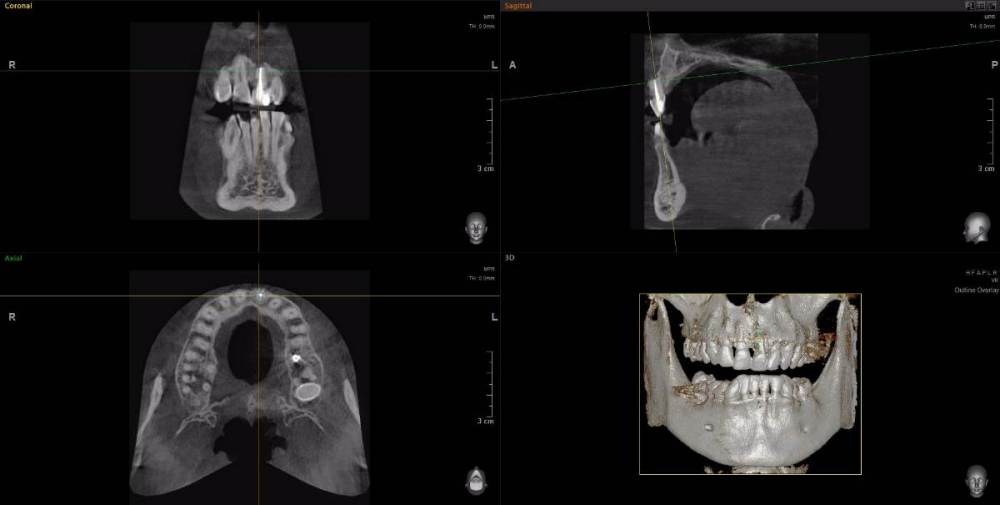

Денис 1 Опубликовано 1 июля, 2021 Поделиться Опубликовано 1 июля, 2021 Здравствуйте. Проблема с передним верхним резцом, кариес под десной. Прошу прокомментировать по КТ https://disk.yandex.ru/d/jRQy8r-N66_CQg возможно ли сохранение зуба в таком состоянии? Я извиняюсь что сразу весь образ диска предоставляю, но у меня на компьютер просмотрщик с диска устанавливаться не хочет. Открыл файлы Фотошопом, но там не понятно ничего. Очень не хочется лишиться переднего зуба, по этому пытаюсь разобраться, существует ли технология лечения зуба с поражением корня под десной? Заранее спасибо за участие. Ссылка на комментарий

wladdX Опубликовано 2 июля, 2021 Поделиться Опубликовано 2 июля, 2021 (изменено) На мой взгляд зуб 21 придётся удалять Изменено 2 июля, 2021 пользователем wladdX 2 Ссылка на комментарий

wladdX Опубликовано 3 июля, 2021 Поделиться Опубликовано 3 июля, 2021 Ни малейших Ссылка на комментарий